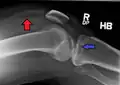

Lipohemarthrosis (presence of fat and blood from bone marrow in the joint space after an intraarticular fracture) seen on X-ray in a person with a subtle tibial plateau fracture

Lipohemarthrosis due to a tibial plateau fracture

Subtle tibial plateau fracture on an AP X ray of the knee

Lipohemarthrosis due to a tibial plateau fracture- A tibial plateau fracture seen on X-ray